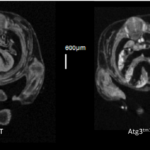

The most intriguing results, Red-Horse said, came from mice which didn’t produce Ino80 in certain heart cells – called endothelial cells – that are the progenitors of blood vessels that feed the muscles of the heart. Without Ino80, the network doesn’t develop properly, and as a result, cardiac muscles couldn’t develop properly either – instead remaining spongy and weak.

It was at this point that the team noticed the similarity between their mice and a form of heart disease called left ventricular non-compaction, the third most common disease of the heart muscle. “It was a complete surprise,” Morrison said.